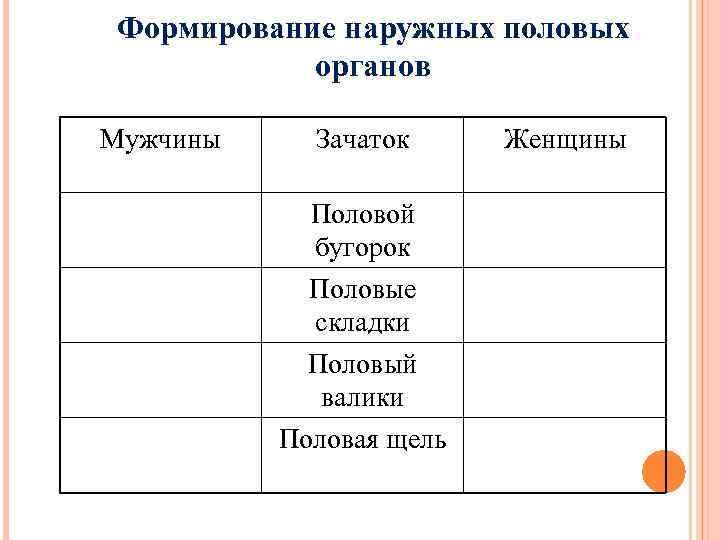

Формирование наружных половых органов Мужчины Зачаток Половой бугорок Половые складки Половый валики Половая щель Женщины

Формирование наружных половых органов Мужчины Зачаток Половой бугорок Половые складки Половый валики Половая щель Женщины